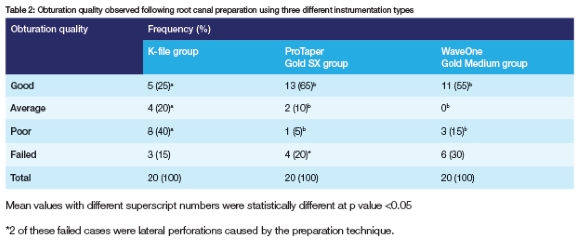

The obturation outcomes observed across the three instrumentation groups differed significantly (p = 0.016). This was followed up by pair wise comparisons for each obturation outcome.

The proportion of "good" obturation outcomes observed with the ProTaper Gold SX group (65%) was significantly higher than observed in the K-file group (25%, p = 0.025) but was similar to the proportion of "good" outcomes observed in the WaveOne Gold Medium group (55%, p = 0.748). The proportion of "average" obturation outcomes was similar across the three groups (Table 2). The proportion of "poor" obturation outcomes was significantly higher in the K-file group (40%) than that observed in the ProTaper Gold SX group (5%; p = 0.020). No other significant differences were observed (Table 2).

In this study, obturation quality was assessed. Three different preparation instrumentations were used to prepare root canals during pulpectomy treatment. The authors found that manual preparation resulted in more "poor" obturation outcomes than the outcomes observed using rotary files. These findings are similar to the results of several other studies.3,9,19,20 No significant differences in obturation quality were observed when comparing rotating or reciprocating files in the preparation of primary teeth.

1. The rotary ProTaper Gold SX file showed superior obturation quality followed by the reciprocating WaveOne Gold Medium file and then conventional ss K-files.

2. The K-file group resulted in the most "poor" and "average" outcomes.

3. There was no significant difference in "failed" outcomes between all three groups.